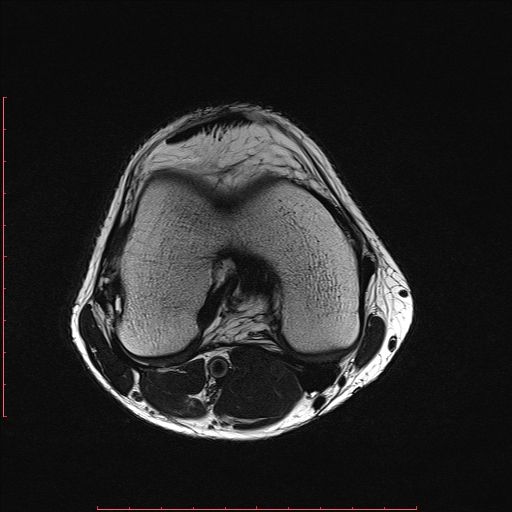

白色文字(排除指定关键词) Imaging Anatomy: interactive PACS-like atlas of radiological anatomy

解剖学模块